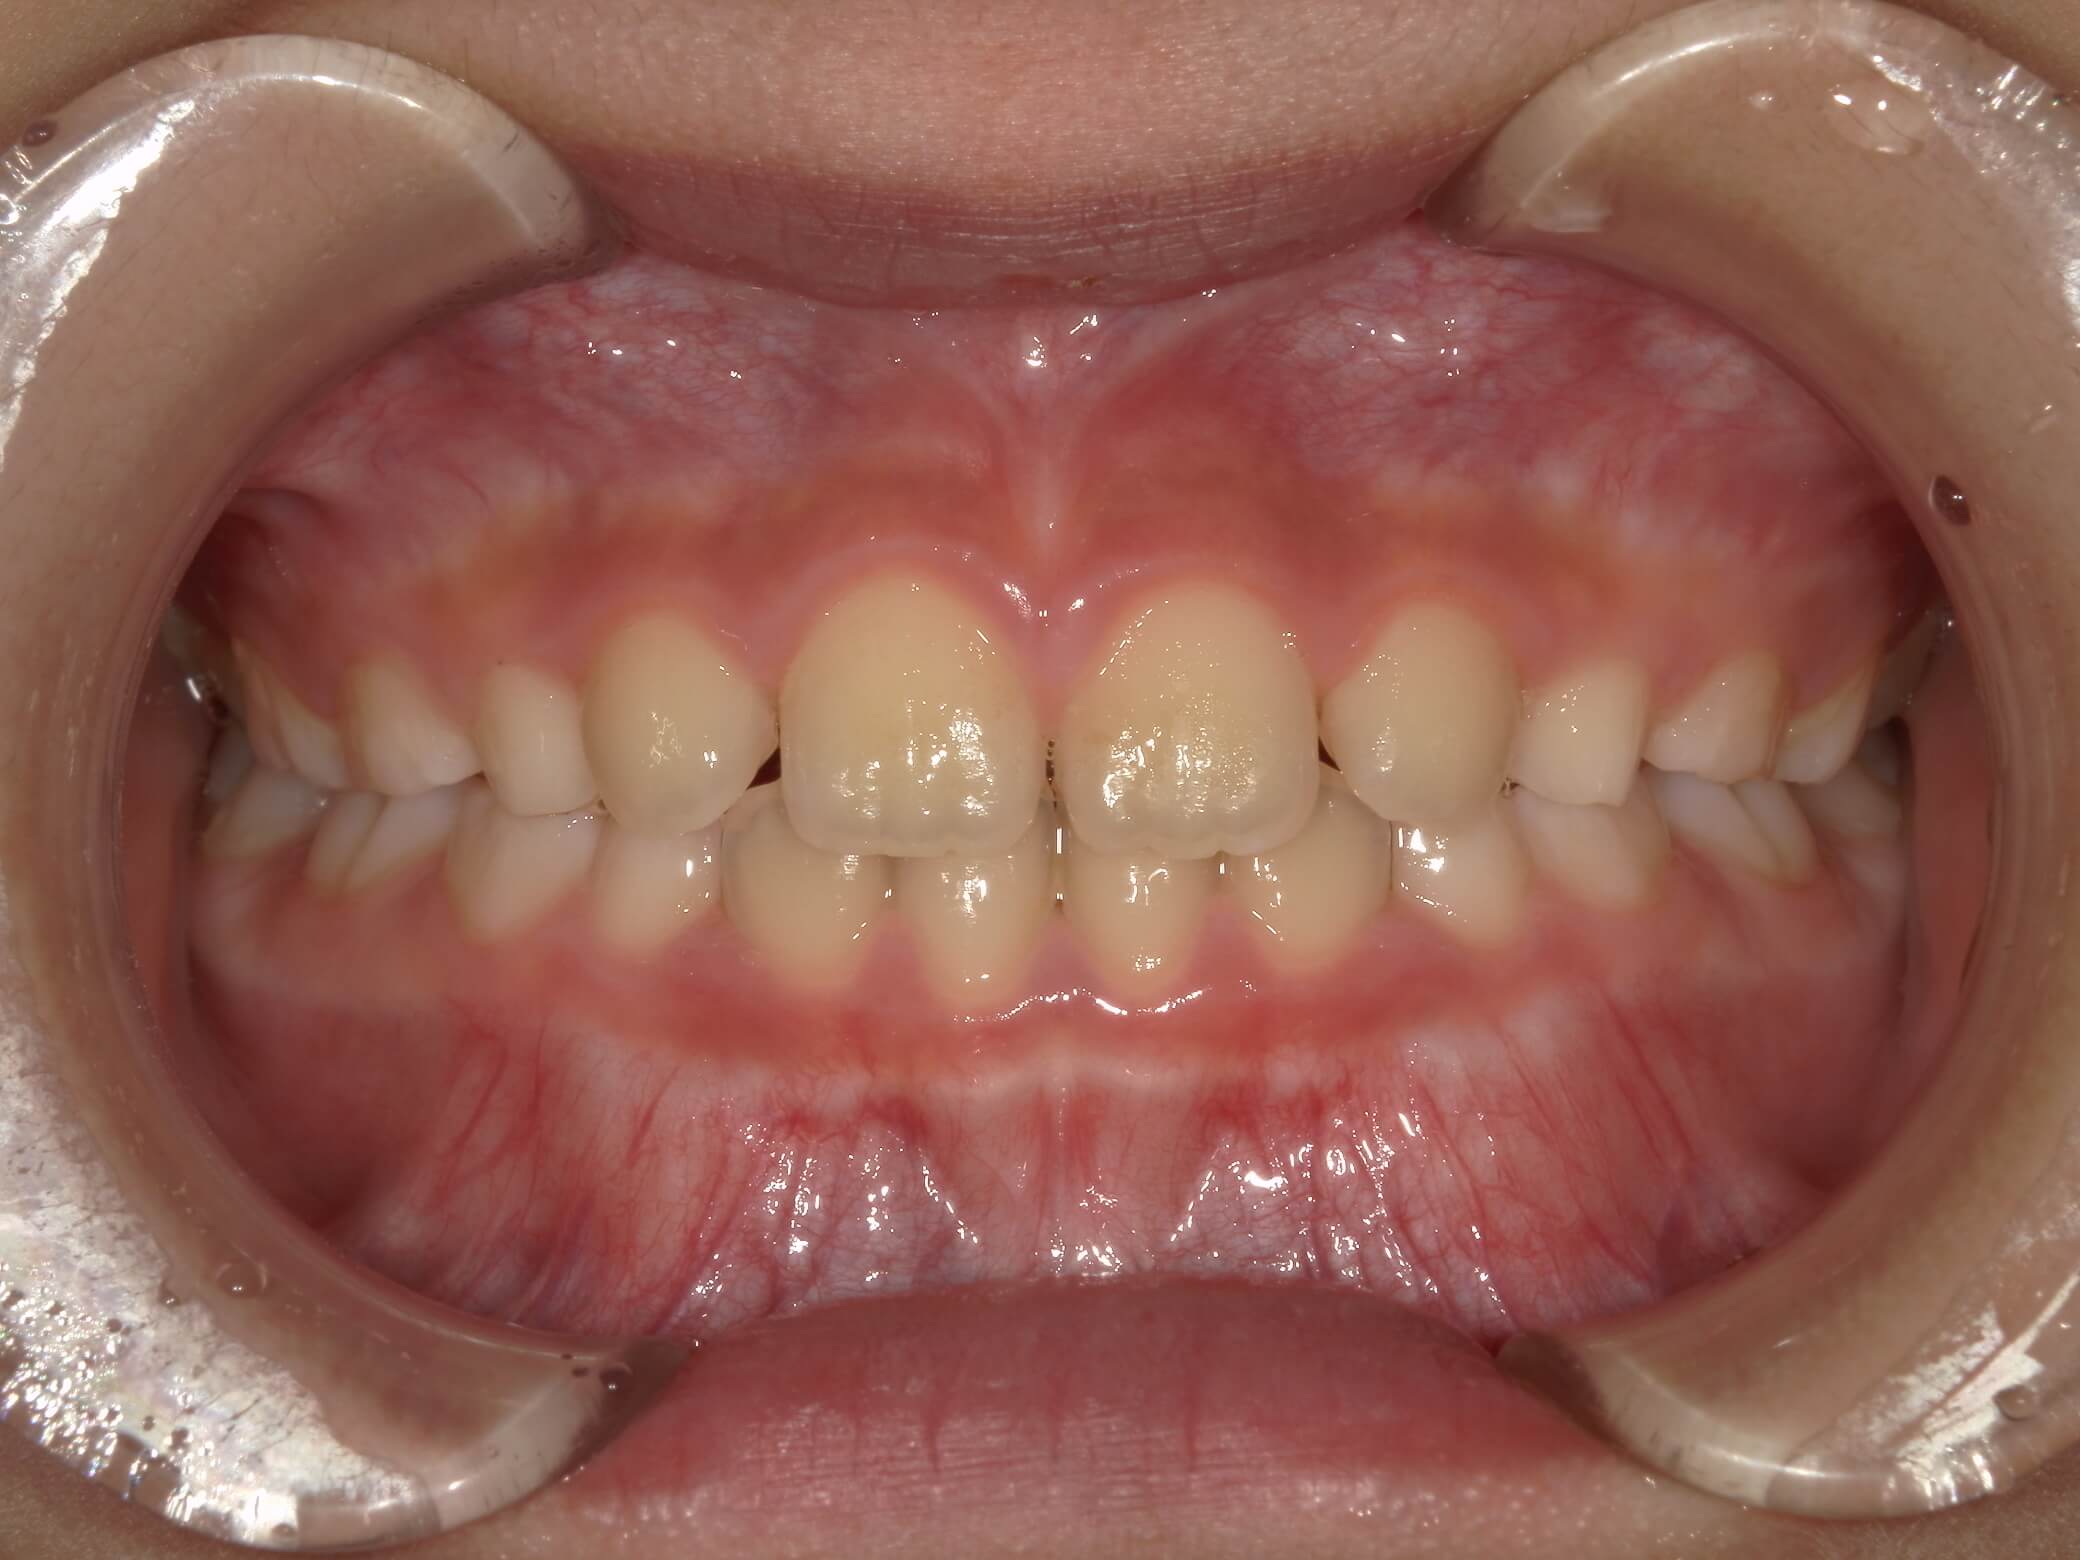

| 年齢・性別 | 男性 |

|---|---|

| 主訴 | 歯の隙間が気になる |

| 治療期間・回数 | 14ヶ月 |

| 費用 | 330,000円(税込) |